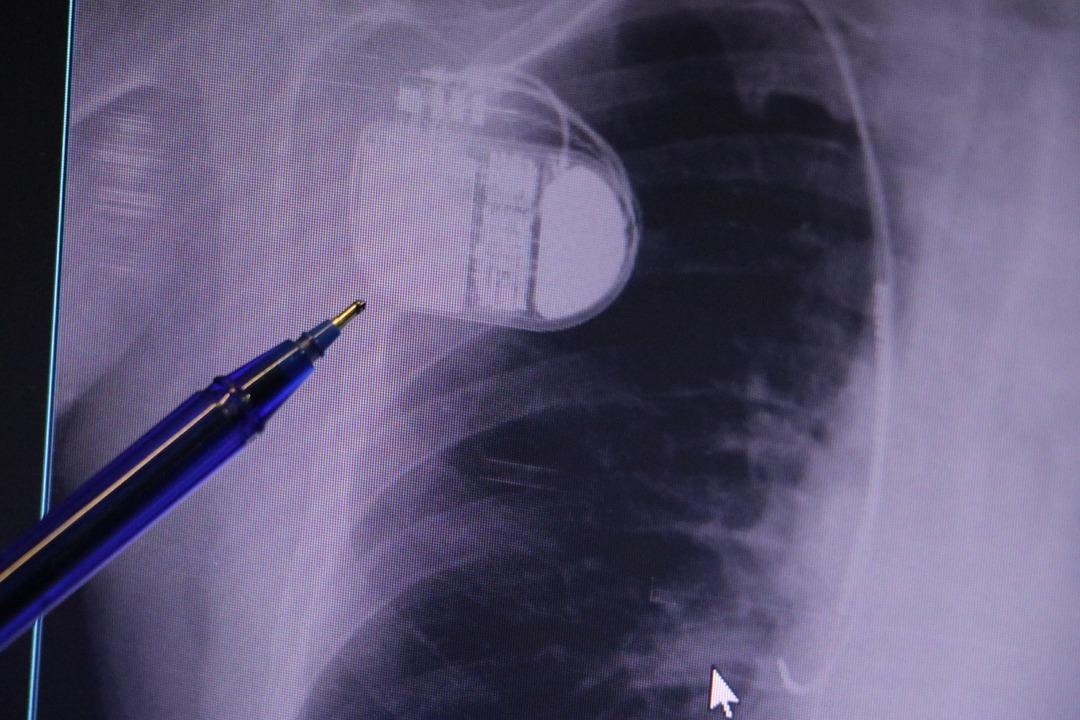

Kalp krizi sonrası kalp dokusunun zarar gördüğünü belirten İsmail Erdoğu, şöyle konuştu: “Kalp hastalığı günümüzde dünyada en sık görülen ölüm nedenlerinden biridir. Kalp hastalıklarının pek çok grubu vardır. Kalp hastalığı dediğimizde sadece kalpte stent bulunan ve damar sorunları olan kişileri kastetmiyoruz. Aynı zamanda hipertansiyon ve şeker hastalığı olan hastalar da kalp hastalığına adaydır. Toplumun yaklaşık %30-35'ini kapsıyoruz. Oldukça yaygın bir hastalıktır ve bu konuda teknolojik ve tıbbi anlamda ciddi gelişmeler yaşanmıştır. Son 30 yılda insanlar kalp rahatsızlığı nedeniyle hastaneye kaldırıldı.” “Hastaneye yattıktan sonra hayatta kalmak artık mümkün. Kalp krizinden kurtulmanın belli bir maliyeti var. Kalp krizinden sonra kalp yetmezliği ortaya çıkıyor. Kalp yetmezliği olan hastalarda aritmiler, ani ölümler gibi sorunlar ortaya çıkabiliyor. Hastaların bu uzun vadeli rahatsızlıklardan kendilerini korumak için mutlaka kalp piline ihtiyaçları var” dedi.

MR makinesine kalp pili takılmasının mümkün olduğunu belirten Erdoğu, şöyle konuştu: “Çok büyük bir ameliyat değil ama yine de ciddi bir cerrahi işlem. Kalp pili tıpta son 30 yılın en büyük gelişmesi. Aslında bilgisayarın minyatürleştirilmiş hali olup insan vücuduna yerleştirilen bir tedavi. İnsan ömrünü önemli ölçüde uzatan bir tedavi. İnsanlar şokla hayata tutunurken, pil olmasaydı öleceğini düşündüğümüz çok sayıda hastamız var. Bu özelliğimiz Kalp pili uygun hastalarda ani ölümü önler, ritmi düzeltecek sağlık uzmanı ya da defibrilatör yoksa hastayı hayatta tutmak mümkün değildir. Hastalarımız “kalp pilim var” dediğinde hastalıktan kurtulurlar. Örneğin mikser kullanmak ya da kolu sallayacak herhangi bir hareket kalp pilini olumsuz etkileyebilir. Soğuk havalarda vücutta meydana gelen şiddetli titremeler kalp pilinin hafızasını karıştırıp gereksiz şoklara neden olabilir.